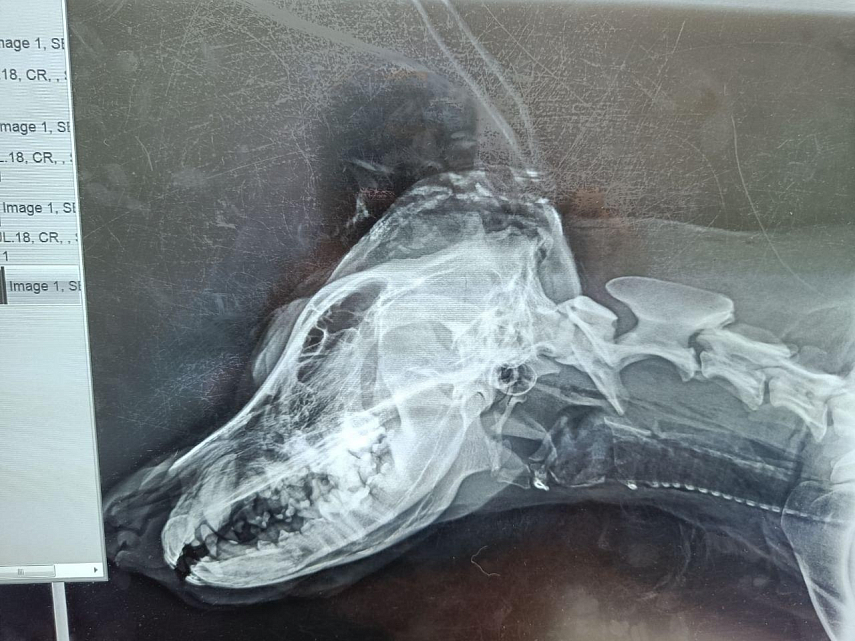

Когда овчарка попала в клинику, врачи не давали никаких прогнозов: слишком тяжелая была травма. Однако пёс одержал победу в битве за жизнь. Он прошел через всё: лечение, дренажи, КТ, прием у офтальмолога, и спустя полторы неделе его не просто выписали, а настойчиво выпроводили из клиники: настолько активен и любопытен он стал.

Выяснить подробности прошлой жизни молодого пса невозможно, как и то, кто с ним жестоко поступил. Заявление в полицию написано, но пока результатов нет. Медики предположили, что страшный удар по голове собаке нанесли топором: слишком мелкие осколки костей пришлось вытаскивать хирургу. Ну, а женщина, благодаря которой пес выжил — она его нашла, позвала помощников и спасателей — до сих пор интересуется его жизнью, регулярно справляется о его самочувствии и пишет в соцсетях волонтеров. Вот так выглядит Абан сейчас.